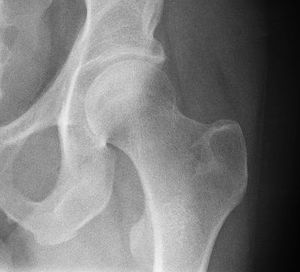

الردف أو الورك Hip منطقة من الجسم تقع بين الجذع والفخذ. ويتشكل مفصل الردف من عظم الردف الذي يتكون من ثلاثة عظام: عظم الحرقفة وعظم الإسك وعظم العانة، ومقدمة عظم الفخذ. وتتكيف مقدمة عظم الفخذ داخل الحُق، وهو تجويف في عظم الورك. ويشكل هذا النسق مفصلاً كرويًا حُقيًا، مما يعطي متانة كبيرة، ويسمح بمدى واسعٍ من الحركة في جميع الاتجاهات. وتحيط عضلات قوية عديدة بالمفصل، تتضمن العضلة الألوية الطرفية، وتكون عريضة ومستديرة في الخلف، والعضلة الألوية الوسطى في الجنب، والعضلة المستقيمة الفخذية الطويلة الشريطية في المقدمة. وتجعل هذه العضلات المفصل ثابتًا قويًا، بحيث يستطيع المرء أن يقف. وهي أيضًا تنقل الأرجل أثناء المشي والجري.

ويُولد العديد من الأطفال، وتجويفهم الوركي قليل العمق. ويطلق على هذه الحالة خلع الورك الولادي. وفي الأعمار المتقدمة، يُصبح عنق عظم الفخذ الذي يوجد أسفل مقدمة عظم الفخذ مباشرة، ضعيفًا، بحيث يسهل كسره. ويمكن إصلاح الكسر، بتثبيت رأس عظم الفخذ على العنق، بمسمار من الصلب المقاوم للصدأ. ويعاني كثير من ضحايا التهاب المفاصل، من ألم مُعجِز في مفصل الردف. وفي هذه الحالات، يمكن استبداله بحُق بلاستيكي وكرة معدنية بالمفصل.